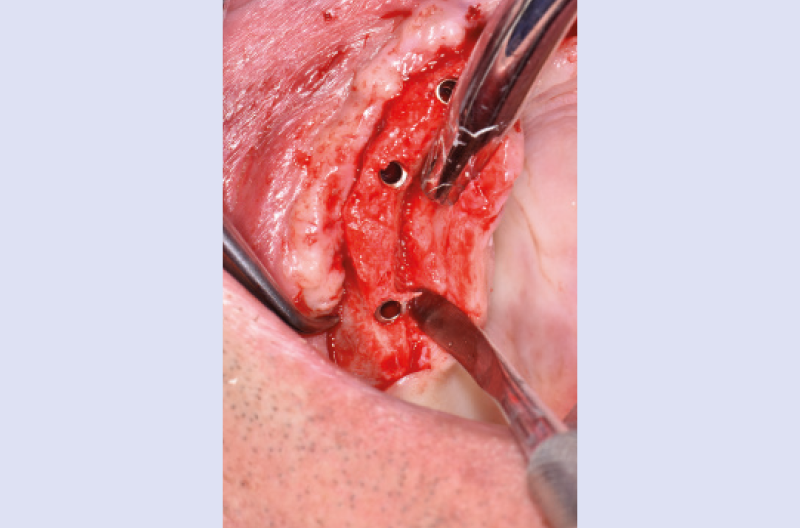

Nel mese di luglio 2019 il paziente ├© stato operato con il contestuale inserimento di 10 impianti, 4 nellŌĆÖarcata inferiore e 6 nellŌĆÖarcata superiore. Ho inserito 4 impianti Max Stability ├ś 3,75 mm nella zona della premaxilla, uno lungo 10 mm e gli altri tre da 12 mm di lunghezza; in regione 15 e 25 ho dovuto invece utilizzare delle frese da osseodensificazione per compattare lŌĆÖosso e traslare la parete mediale del seno mascellare per poter inserire 2 impianti Max Stability ├ś 3,75 L 12 mm inclinandoli lungo la parete stessa. Data la scarsa quantit├Ā e qualit├Ā di osso nel mascellare, ho rinunciato al carico immediato rinviando la procedura della protesizzazione immediata nella fase di riapertura degli impianti ad osteointegrazione avvenuta (Figg. 1-14).

Fig. 6 – Isolamento del nervo palatino

Fig. 9 – Osseodensificazione e traslazione parete mediale del seno mascellare di destra

Fig. 10 – Impianto in regione 15 inclinato lungo la parete mediale del seno

Fig. 11 – Osseodensificazione e traslazione parete mediale del seno mascellare di sinistra